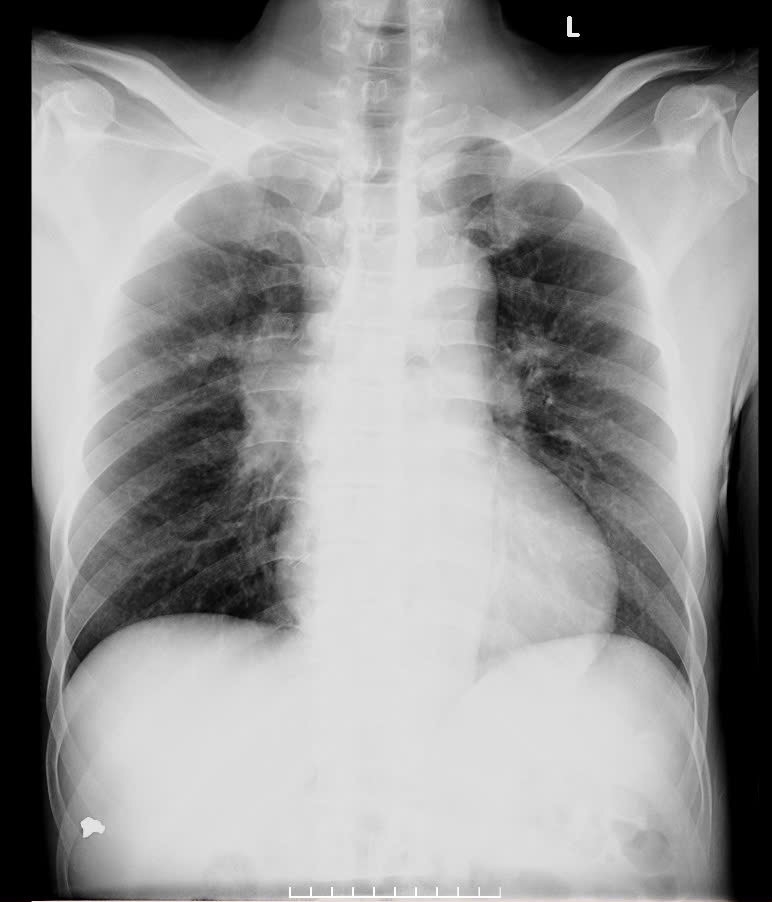

Ngày 1/8, Bệnh viện Đa khoa Bắc Giang tiếp nhận bệnh nhân cho biết: sau khi thăm khám ban đầu, ông Lưu được chỉ định chụp xquang phổi, sau đó bệnh nhân nhận được kết quả là có một khối u lạ trong phổi và được chỉ định chụp cắt lớp vi tính, thì phát hiện có khối u bên phổi trái gây tổn thương ở hai bên phổi, u tăng sinh nghi ngờ là ung thư phổi. Tiếp đó, ông Lưu được làm nội soi phế quản, sinh thiết tổn thương ở niêm mạc phế quản, phát hiện mắc ung thư phổi di căn tại phổi, gan. Bệnh bước vào giai đoạn muộn nên phác đồ điều trị không tối ưu, tiên lượng rất xấu.

Bệnh viện Đa khoa Bắc Giang cung cấp hình ảnh Xquang của bệnh nhân Trần Văn Lưu